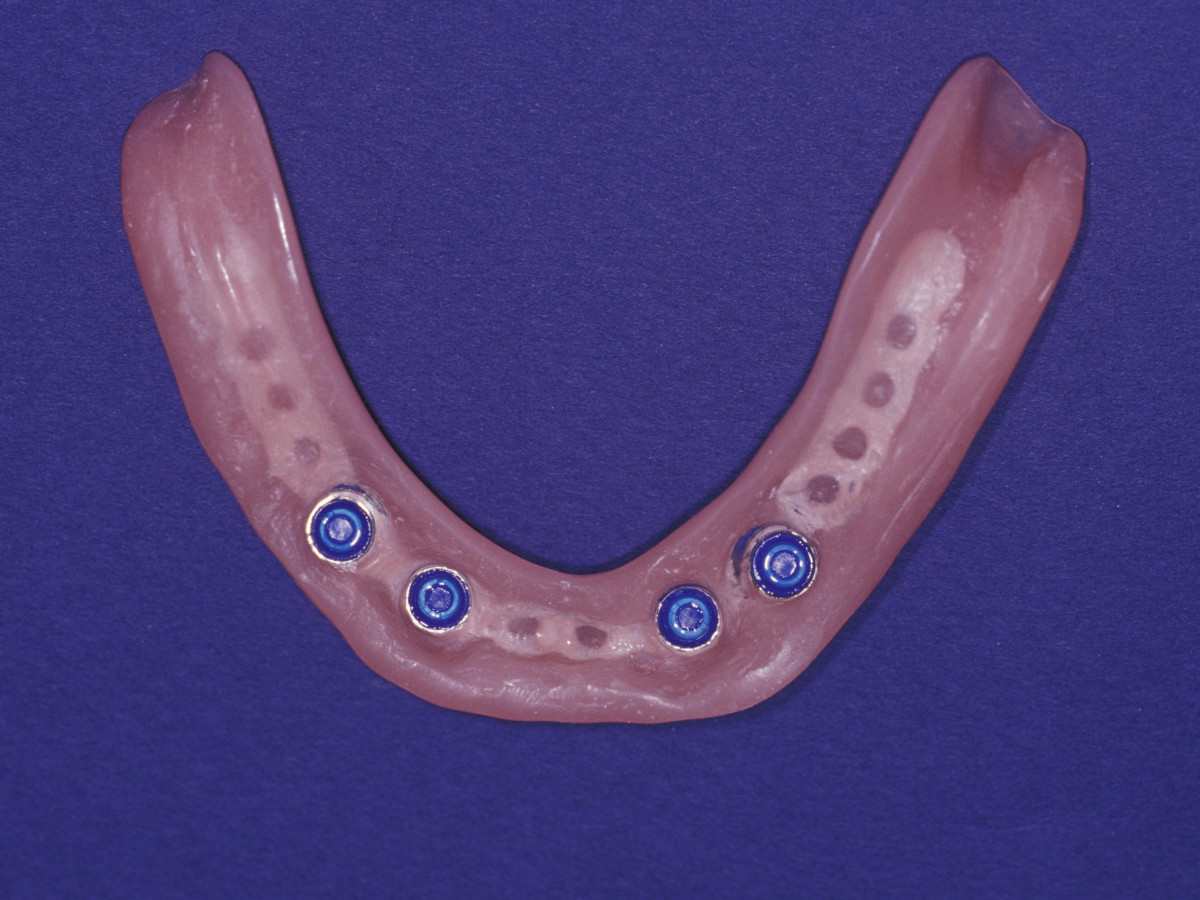

Современные съемные протезы на локаторах: Фото и примеры